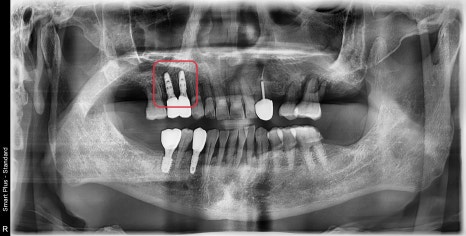

이식재가 충분히 굳어지기를 기다린 후

보철까지 완성한 사진입니다.

다행히 수술 약 4개월 후 3D CT에서

임플란트 주변으로 흰색으로 보이는 뼈가 생성된 것을 확인할 수 있었습니다.

현재 1년이 지난 전체 사진에서도 특별한 문제는 없어 보입니다.

수술 후 4달 후 사진입니다.

임플란트 주변에 흰색 뼈가 생성된 것을 볼 수 있었습니다.

뼈와 임플란트의 고정성 평가에서도 좋은 수치를 나타내 보철치료까지 마무리했습니다.

최근 내원하셨을때 사진입니다.

브릿지치아 중 앞 치아는 발치 없이 재보철하여 보존하였고

뒤에 2개의 공간에 임플란트를 식립했습니다.

이 환자분 같은 경우 2년이 지난 현재까지

정기검진을 오시며 잘 사용하고 계십니다.